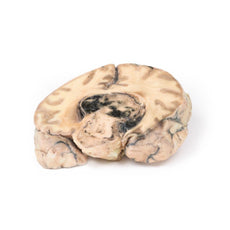

3D Printed Glioma Grade 3-4, Causing Papilloedema

The specimen shows a large intracerebral lesion, which has obliterated the lateral ventricles and

the inner 2/3 of the internal capsule and basal ganglia on the right side. It is infiltrating across the corpus

callosum and distorting the aqueduct. The tumour is fairly well demarcated and vascular with numerous areas of

haemorrhage and necrosis, causing its mottled variegated appearance.